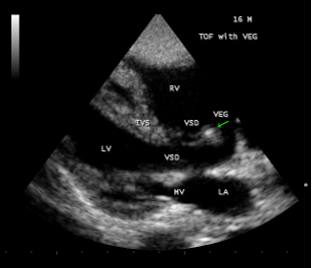

A 16-year-old cyanotic male was admitted with altered sensorium in the intensive care unit. He was diagnosed as Tetralogy of Fallot and advised corrective surgery earlier. He was afebrile and his pulse rate was 64 bpm and blood pressure 100/60 mmHg. He had headache, vomiting episodes and stiff neck for the past 3 days. Blood chemistry revealed normal. ECG and X-ray chest as in Figure 1 (boot-shaped heart) were consistent with Tetralogy of Fallot. Physical examination revealed uniform central cyanosis with clubbing, 2/6 systolic murmur in the left second intercostal space and a single second sound. Echocardiography revealed a non-restrictive, large, malaligned VSD (ventricular septal defect), biventricular aorta as shown in Figure 2. A large vegetation was attached to the crest of interventricular septum (IVS) as in Figures 3 and 4.

Figure 3: showing “the vegetation” (arrow) attached to the crest of IVS (interventricular septum) in a 16 –year old boy with Tetralogy of Fallot.

The four components of TOF are ventricular septal defect (VSD), aortic override, right ventricular outflow tract obstruction and right ventricular hypertrophy. In unrepaired TOF, pathophysiology depends on the degree of RVOT obstruction. When obstruction of right ventricular outflow is mild to moderate and a fairly balanced shunt operates across VSD and the patient may not be cyanotic , called as “acyanotic” or “pink” tetralogy of Fallot. The patient may remain relatively asymptomatic until the balance between pulmonary and systemic circulation is disturbed. Echocardiography plays a key role in the diagnosis of infective endocarditis (IE) in TOF. Vegetation may occur on pulmonary and tricuspid valves [42] and a large vegetation occluding the VSD had been reported [43]. In this patient, a large vegetation attached to the crest of interventricular septum was shown in Figures 3 and 4.